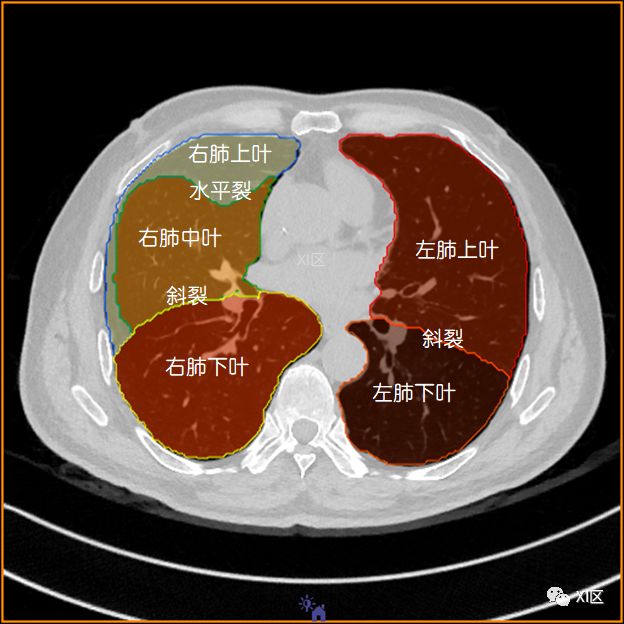

左肺借斜裂成上、下两叶;右肺借斜裂和水平裂成上、中和下叶三叶。

横断位